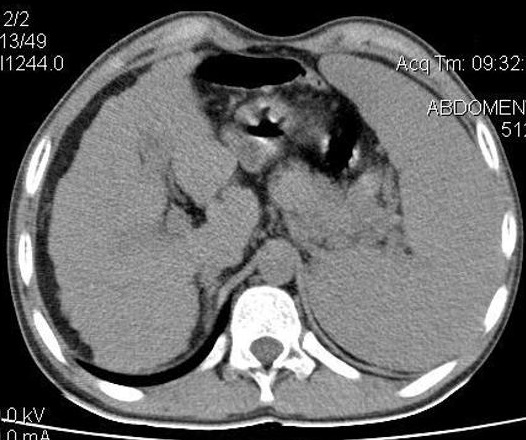

Image TDM de la

cirrhose du foie : Technique radiologique moins

sensible de dignostic cirrhose du foie au debut . Au

stade avance image radiologique TDM de la cirhose du foie

est : Parenchyme du foie est heterogene , hypertrophie

du lobe caude , index C/RL > 0.65 et signe de hypertension

portale : dilatation de la veine porte , veine

splenique , splenomegalie et image de thrombus veineuse .

Image

radiologique TDM d'une cirrhose du foie en coupe

axiale . Le parenchyme et surface du foie est en

nodulaire , heterogene . La lobe caude est

hypertrophie , splenomegalie legere . Index C/RL est

> 0.66 ( cirrhose du foie ) |